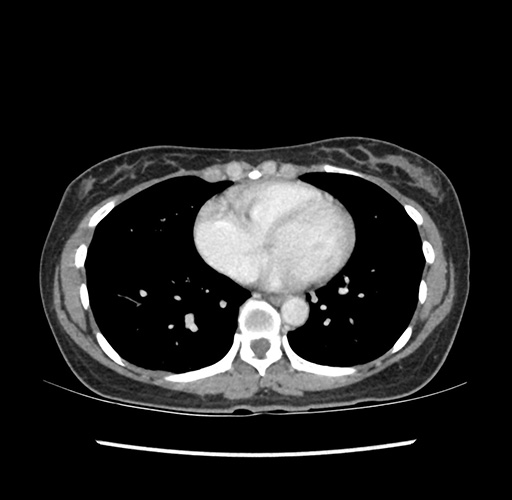

Imaging Analysis

Look through the patient's CT scan to identify any areas of concern for the necessary procedure.

Based on your CT findings, which issue(s) would give reason for "planned slowing down moment(s)" in this case?